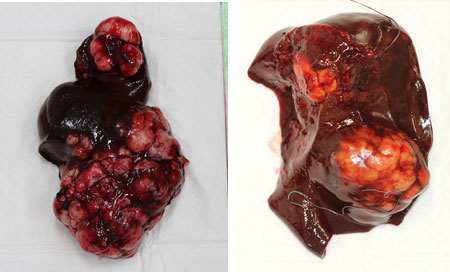

摘出した内側および外側右葉に発生した肝臓腫瘍です。

術後経過は良好ですが、残った肝臓にも小さい腫瘍の肝内転移が手術時に見つかりました。そのためこのわんちゃんは完治が難しいですが今後は残った腫瘍が出来るだけ大きくならないように抗がん治療を受けています。